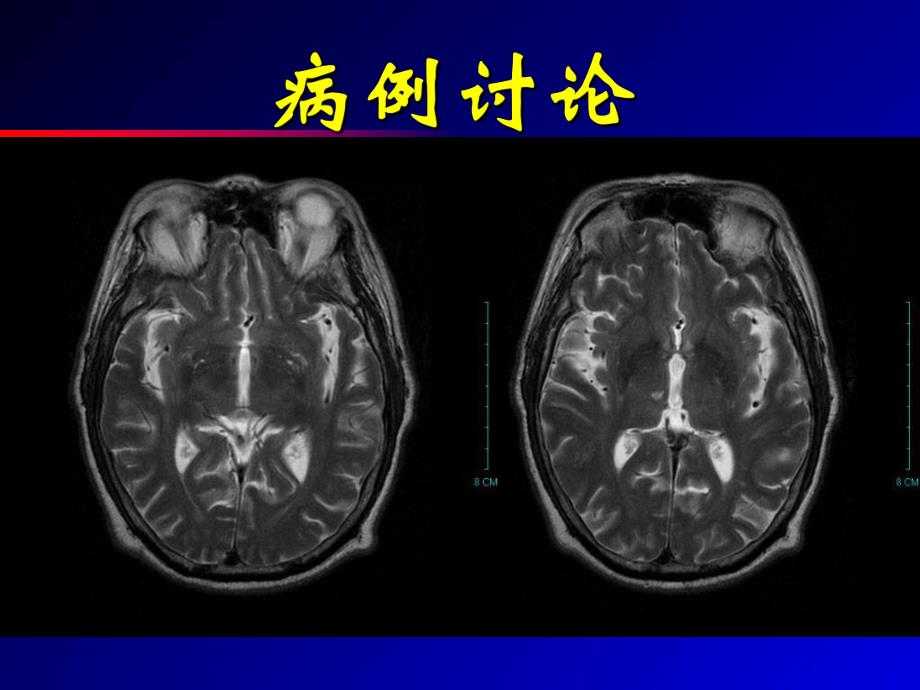

1、血管周围间隙 1.患者男性,57岁,右利手,主因突发头痛10天,9月2日门诊以“颅内病变性质待查”收入院。现病史:患者8-22上午10时工作时突发右侧后枕部剧烈头痛,无头晕、恶心及其它神经系统症状,在当地医院行CT检查发现左额顶颞大片低密度,原因待查,随来我院明确诊治。病例特点病例特点既往史:高血压病史10余年,长期服用降压药,但欠规则。有家族性高血压史控制不理想;阑尾炎病史20年,腰间盘突出病史3年;磺胺类药物过敏史,吸烟史30年,20支天。病例特点病例特点入院查体:T370C,P84次/分,R20次/分,Bp130/80mmHg。神清语利,双瞳等大等圆,对光反应灵敏,额纹对称,伸舌居中;四

2、肢肌力5级;神经反射正常,余神经系统查体未见明显异常。辅助检查实验室辅助检查实验室血尿便常规、肝肾功能、电解质均正血尿便常规、肝肾功能、电解质均正常,抗心磷脂抗体阴性,免疫全套常,抗心磷脂抗体阴性,免疫全套、肿瘤、肿瘤6项正常范围项正常范围。脑脊液常规脑脊液常规生化、病毒全套正常,血脑脊液囊生化、病毒全套正常,血脑脊液囊虫酶标阴性。余实验室检查未见特虫酶标阴性。余实验室检查未见特殊表现。殊表现。血管超声:右颈内动脉硬化斑块形血管超声:右颈内动脉硬化斑块形成,成,双侧双侧ICA供血参数大致正常供血参数大致正常,RVA血流量低,双侧锁骨下动血流量低,双侧锁骨下动脉血流通畅。脉血流通畅。TCD:颅内

3、血管未见明显异常。颅内血管未见明显异常。脑电图:广泛轻度异常。脑电图:广泛轻度异常。辅助检查超声脑电图辅助检查超声脑电图外院及我院外院及我院CT提示:左侧额顶提示:左侧额顶叶皮层下、胼胝体区可见多发叶皮层下、胼胝体区可见多发异常低密度影。增强后:低密异常低密度影。增强后:低密度病变未见明显强化。度病变未见明显强化。辅助检查辅助检查CT辅助检查辅助检查CT辅助检查辅助检查CT平扫:左侧额顶颞叶、胼胝体及右平扫:左侧额顶颞叶、胼胝体及右侧半卵圆中心区可见多发囊性异侧半卵圆中心区可见多发囊性异常信号影,边界清楚锐利。常信号影,边界清楚锐利。诊断:异常扩张的血管周围间隙诊断:异常扩张的血管周围间隙。辅

4、助检查辅助检查MRI辅助检查辅助检查MRI辅助检查辅助检查MRI辅助检查辅助检查MRIDSA:未见明显异常。未见明显异常。辅助检查辅助检查DSA辅助检查辅助检查DSA辅助检查辅助检查DSA本病例结合临床表现、实验室本病例结合临床表现、实验室检查及影像学检查结果,最后检查及影像学检查结果,最后出院诊断为:颅内多发异常密出院诊断为:颅内多发异常密度影,考虑为异常扩张的血管度影,考虑为异常扩张的血管周围间隙。周围间隙。定性诊断定性诊断 血管周围间隙是中枢神经系统除毛细血管周围间隙是中枢神经系统除毛细血管外的小血管周围的一种间隙。过血管外的小血管周围的一种间隙。过去曾认为它与蛛网膜下腔之间存在着去曾认